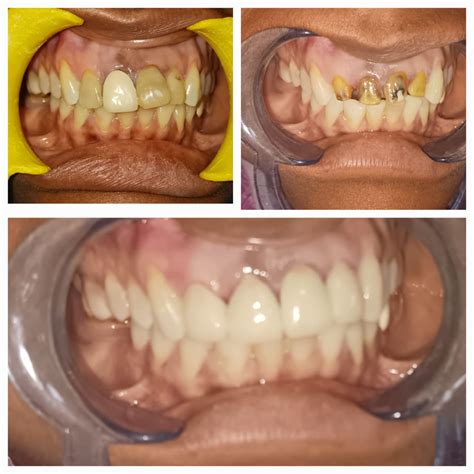

Dental Crowns – A Restorative Option for Extensive Damage

For severely chipped or damaged teeth, dental crowns may be necessary. Dental crowns are custom-made caps that completely cover the damaged tooth, providing strength, protection, and aesthetic improvement. They are often recommended when the chip is extensive or when the tooth has undergone root canal treatment.

The cost of dental crowns can range from $800 to $2,500 per tooth, depending on factors such as the type of material used (such as porcelain, metal, or ceramic), the complexity of the case, and the dentist’s fees. Dental insurance may cover a portion of the cost for dental crowns, especially if they are deemed necessary for restoring the tooth’s function.

In conclusion, treatment options for chipped teeth vary in terms of cost and suitability for different cases. Dental bonding is an economical choice for minor chips, while veneers offer a natural-looking and durable solution for moderate to severe chips. Dental crowns, on the other hand, are recommended for extensive damage and can provide both functional and aesthetic benefits. Consult with a dentist to determine the most suitable treatment option for your chipped tooth and to get an accurate cost estimate.